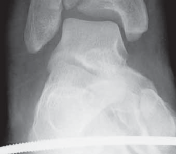

--- A B ### FIG 2 • A,B. CT images from 43-C3 plafond injuries demonstrating typical fracture patterns with anterolateral, medial malleolus, and posteromedial fragments. Variable amounts of central or anterocentral articular impaction and comminution are commonly seen.

C TECH FIG 1 • A–C. Imaging of 43-C3 plafond injury with anteromedial cortical split allowing best access to injury through anteromedial A B approach.